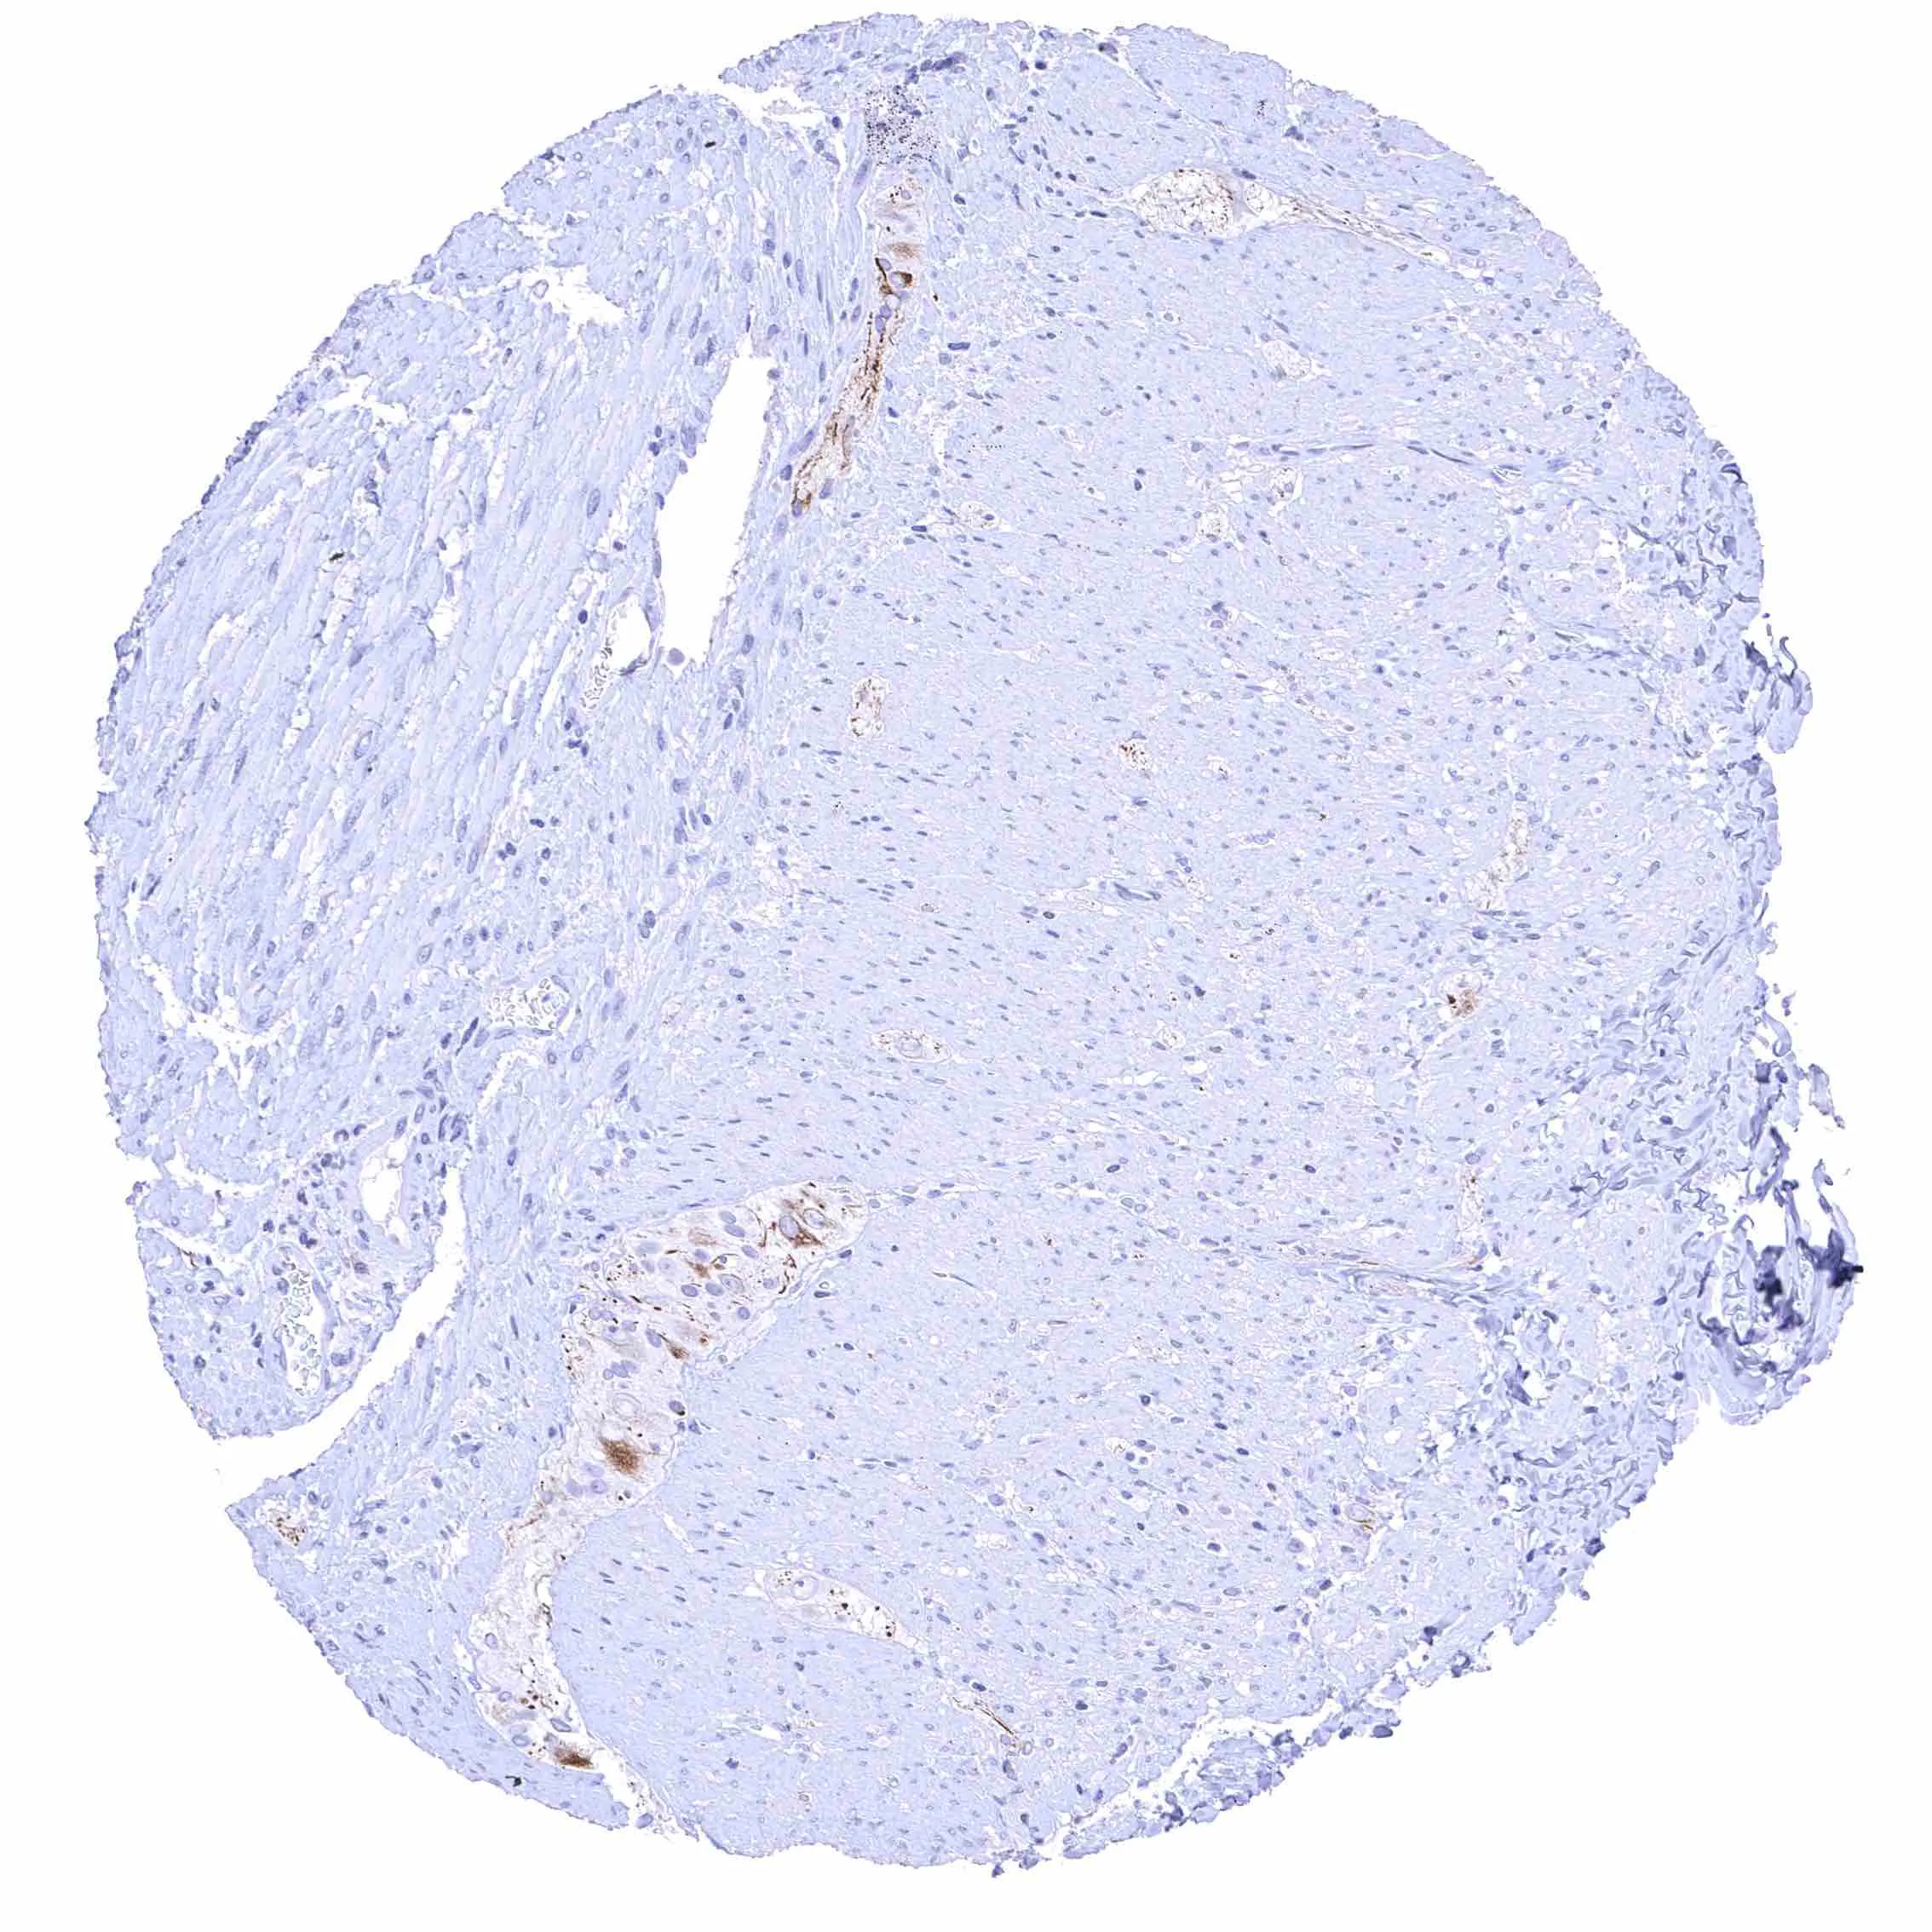

Prostate